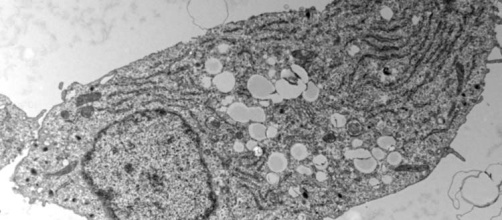

The role of lipids in the development of Alzheimer’s disease

The unexpected benefits of fat in type 2 diabetes